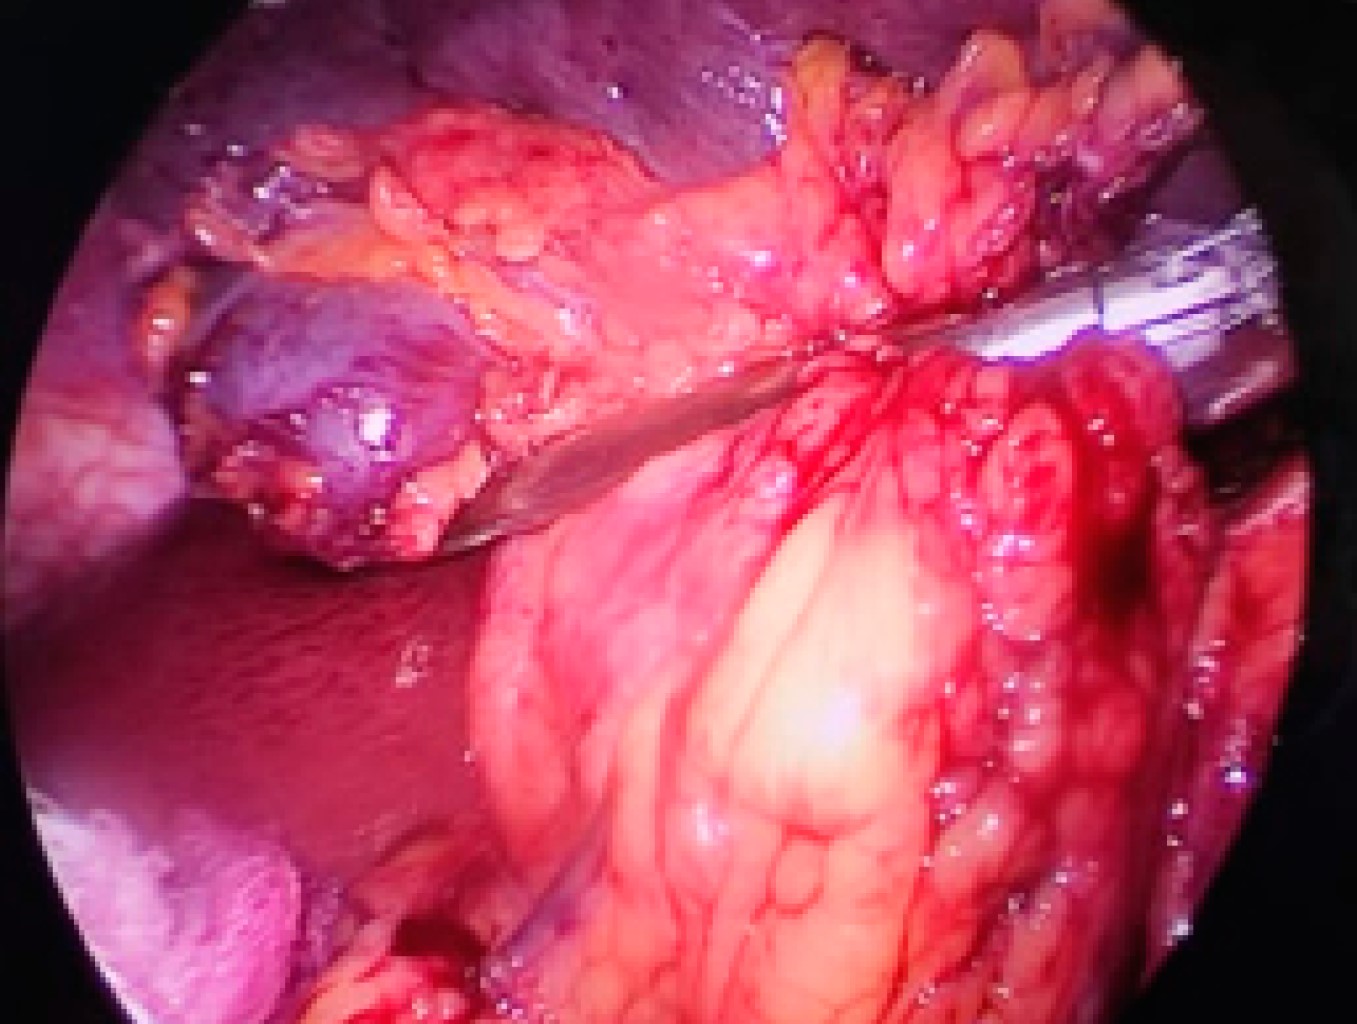

Elective laparoscopic splenectomy at the National Northeastern Medical Center. Case series report

Aguirre-Flores K, Mazariegos-Gutiérrez UE, Gómez-Arenas SR, Nacud-Bezies YA

Introduction: since the early 1990's, laparoscopic splenectomy has been performed with excellent results in multiple centers. This study reports the experience with this procedure at the National Northeastern Medical Center. Material and methods: retrospective and observational study of patients surgically treated with laparoscopic splenectomy in the period from March 2018 to May 2022, analyzing demographic, diagnostic, preoperative, transoperative and postoperative variables. Results: the database of 27 patients was reviewed, of whom 85.18% were women, and the average age was 36.4 years. The main diagnosis was immune thrombocytopenic purpura in 73.30%. The average operative time was 126.9 minutes. The average length of hospital stay after surgery was 25.3 hours. Only one patient presented surgical site infection. The percentage of patients with complete response to treatment was 85.18% and 14.82% presented a partial response with a diagnosis of immune thrombocytopenic purpura associated with myelodysplastic syndrome, currently in bone marrow transplant protocol. Conclusions: at the National Northeastern Medical Center, laparoscopic splenectomy is the surgical procedure of choice in patients with hematologic pathology refractory to second and third line medical treatment.

Figure 2